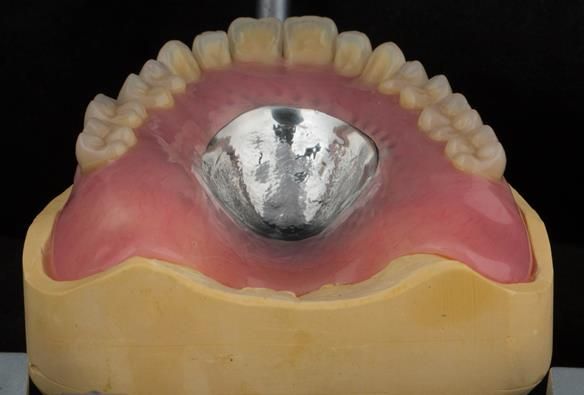

- Definitive dentures (Mk 2) – complete upper metal reinforced and lower cobalt chromium based partial of hygienic Scandinavian design to be made 9 - 12 months after extractions of all upper teeth and LR5 and LL4

The clinical situation and treatment process is shown in detail below with photographs.

The patient has been successfully rehabilitated and is now having periodontal maintenance from Syed Abad, Specialist in Periodontics at the practice. His quality of life has improved considerably. The clinical prosthodontics was provided by me and the technical work by Rowan.